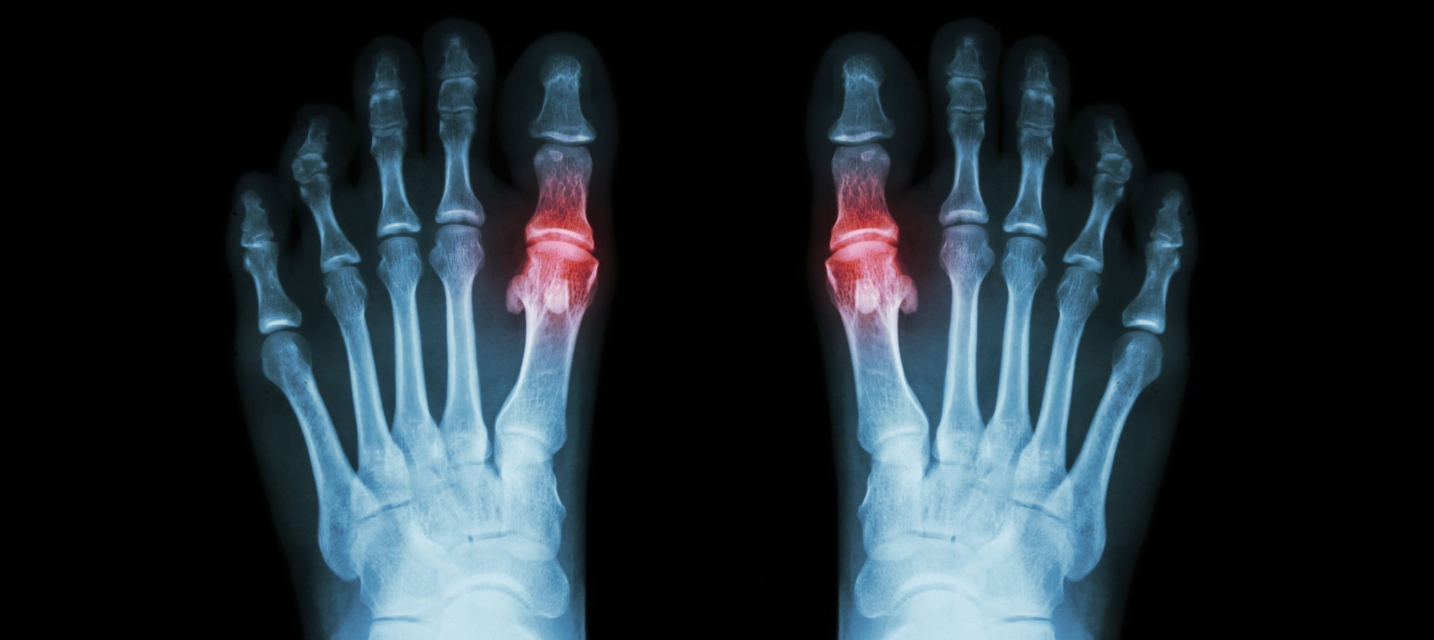

L’arthrite de l’articulation du gros orteil (articulation métatarso-phalangienne) est une affection courante. L’hémiarthroplastie est une option chirurgicale qui suppose l’installation d’une prothèse dans l’os pour réduire la douleur et améliorer le mouvement et la fonction. La prothèse synthétique offre une nouvelle surface lisse pour favoriser les mouvements corrects de votre orteil et éviter le contact entre les os.